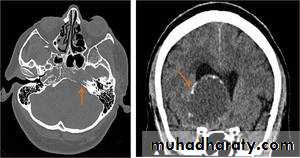

Haemangioblastoma

Arise from per vascular pericyte

GII to III in their malignancy

Age between 30 -65 Y , represent 10 % of PFT

Intra axial t. arise from the cerebellum , brain stem ,spinal cord

CT finding , as smooth walled cystic lesion with enhancing mural nodule rarely calcified .